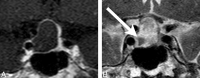

Background and purpose: Cystic pituitary adenomas may mimic Rathke cleft cysts when there is no solid enhancing component found on MR imaging, and preoperative differentiation may enable a more appropriate selection of treatment strategies. We investigated the diagnostic potential of MR imaging features to differentiate cystic pituitary adenomas from Rathke cleft cysts and to develop a diagnostic model.

Materials and methods: This retrospective study included 54 patients with a cystic pituitary adenoma (40 women; mean age, 37.7 years) and 28 with a Rathke cleft cyst (18 women; mean age, 31.5 years) who underwent MR imaging followed by surgery. The following imaging features were assessed: the presence or absence of a fluid-fluid level, a hypointense rim on T2-weighted images, septation, an off-midline location, the presence or absence of an intracystic nodule, size change, and signal change. On the basis of the results of logistic regression analysis, a diagnostic tree model was developed to differentiate between cystic pituitary adenomas and Rathke cleft cysts. External validation was performed for an additional 16 patients with a cystic pituitary adenoma and 8 patients with a Rathke cleft cyst.

Results: The presence of a fluid-fluid level, a hypointense rim on T2-weighted images, septation, and an off-midline location were more common with pituitary adenomas, whereas the presence of an intracystic nodule was more common with Rathke cleft cysts. Multiple logistic regression analysis showed that cystic pituitary adenomas and Rathke cleft cysts can be distinguished on the basis of the presence of a fluid-fluid level, septation, an off-midline location, and the presence of an intracystic nodule (P = .006, .032, .001, and .023, respectively). Among 24 patients in the external validation population, 22 were classified correctly on the basis of the diagnostic tree model used in this study.